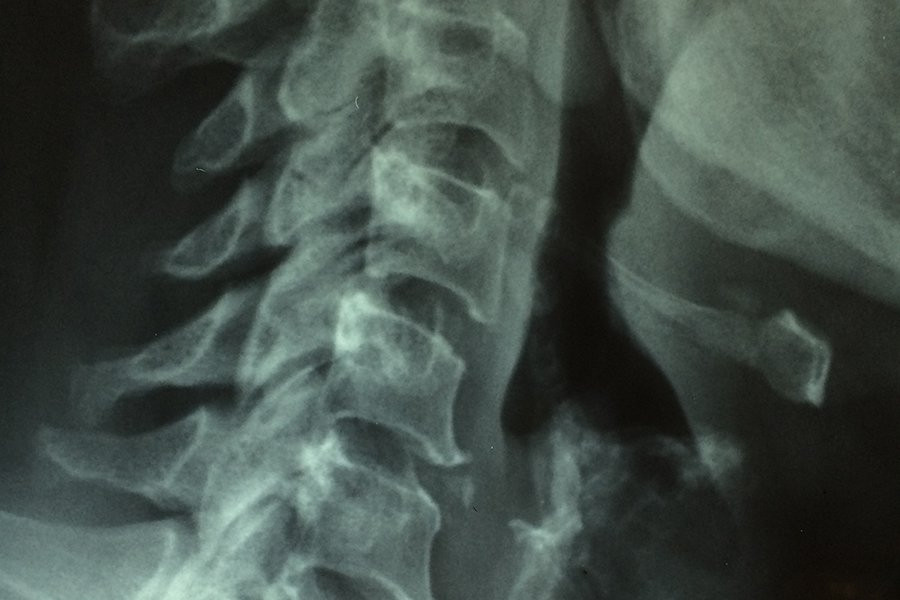

Центральная нервная система (ЦНС) имеет очень ограниченные способности к исцелению. Травмы в результате дорожно-транспортных происшествий, спортивных инцидентов или аутоиммунных заболеваний, таких как рассеянный склероз, часто приводят к постоянным функциональным нарушениям. Независимо от причины травмы, организм реагирует формированием границы вокруг поврежденной ткани, которая в конечном итоге становится постоянной рубцовой тканью.

Хотя рубцовая ткань запечатывает поврежденный участок, она также предотвращает функциональное восстановление. После травм спинного мозга рубцовая ткань блокирует регенерацию нервных волокон, соединяющих головной мозг с телом, что приводит к параличу после тяжелых травм.